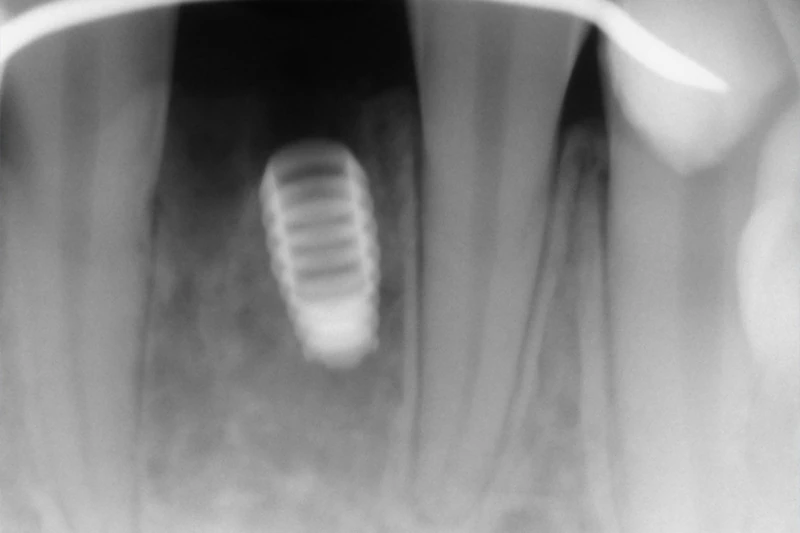

The Bicon Implant Difference

At Taylor and Associates Family & Implant Dentistry, we often use the Bicon implant system because of its stability, longevity, and natural appearance. While all dental implants replace missing tooth roots, the implant's design plays an important role in comfort and long-term success.

Bicon implants use a secure locking taper connection rather than small screws. This creates a tight, bacteria-resistant seal and helps eliminate the dark metal lines sometimes seen at the gumline with other implant systems. The design also provides strong support while allowing shorter implants to be used in many cases, which may reduce or even avoid the need for bone grafting procedures.